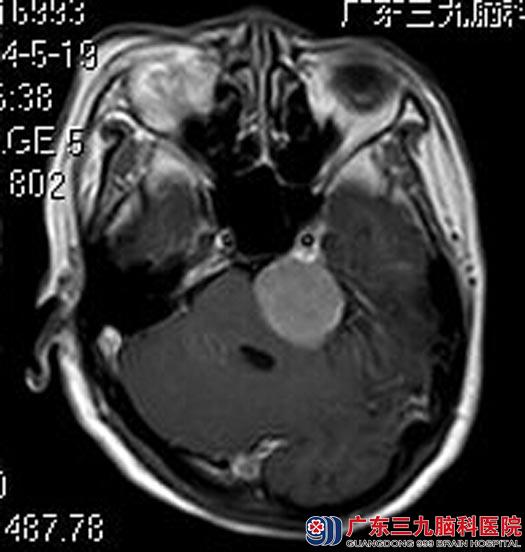

广东三九脑科医院进一步MR检查提示:左侧桥小脑角区一团块状占位性病变,大小约3.45cm×2.62cm×3.38cm,脑干及四脑室受压、变窄。

手术前